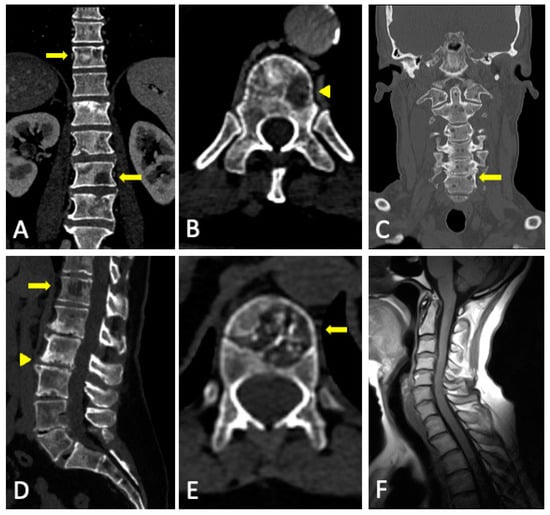

4. WBMRI

4.2. Disease Patterns

- Apparently normal bone marrow.

- Focal pattern: Focal myeloma infiltration was defined by circumscribed areas of high SI on STIR and T2WI. These corresponded to areas of low SI or, in a few cases, isointense signal upon an unenhanced T1WI [31]. The definition of focal lesion has evolved lately through the use of sequences such as DWI and Dixon. Therefore, focal lesions are defined as lesions greater than 5 mm hyperintense to background muscle at a b-value of 900 s/mm2, using ADC maps and confirming these findings with the corresponding Dixon sequences [32].

- Micronodular pattern: The micronodular or variegated or “salt and pepper” pattern presents a widespread heterogeneity with tiny nodular areas of altered diffusion signal (<5 mm) and T1WI hypointensities with preserved normal marrow between them [26].

- Diffuse pattern: Diffuse disease can be suspected from a diffuse decreased signal on T1WI (either iso- or hypointense to intervertebral discs and muscle) and a diffuse increased signal throughout the marrow on T2FSWI, STIR, or high b-value DWI. Marrow ADC values above 600–700 μm2/s in a nontreated and newly diagnosed patient with MM could be used to increase confidence for the diagnosis of diffuse marrow involvement [33] (Figure 7). Due to potential false-positive findings, diffuse disease in imaging must be supported by bone marrow trephine biopsy [26].

- Mixed pattern: This pattern combines diffuse and focal patterns.